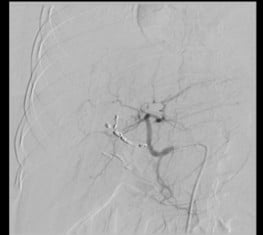

Selective catheterization of right hepatic artery branches distal to the pseudoaneurysm was done with the microcatheter-guidewire combination. Embolization of distal branches as well as the segment proximal to the pseudoaneurysm was done with multiple microcoils. Post-embolization angiogram showed flow stasis in the pseudoaneurysm without any anterograde or retrograde filling (Figure 3).

Figure 3: Angiography post-coiling